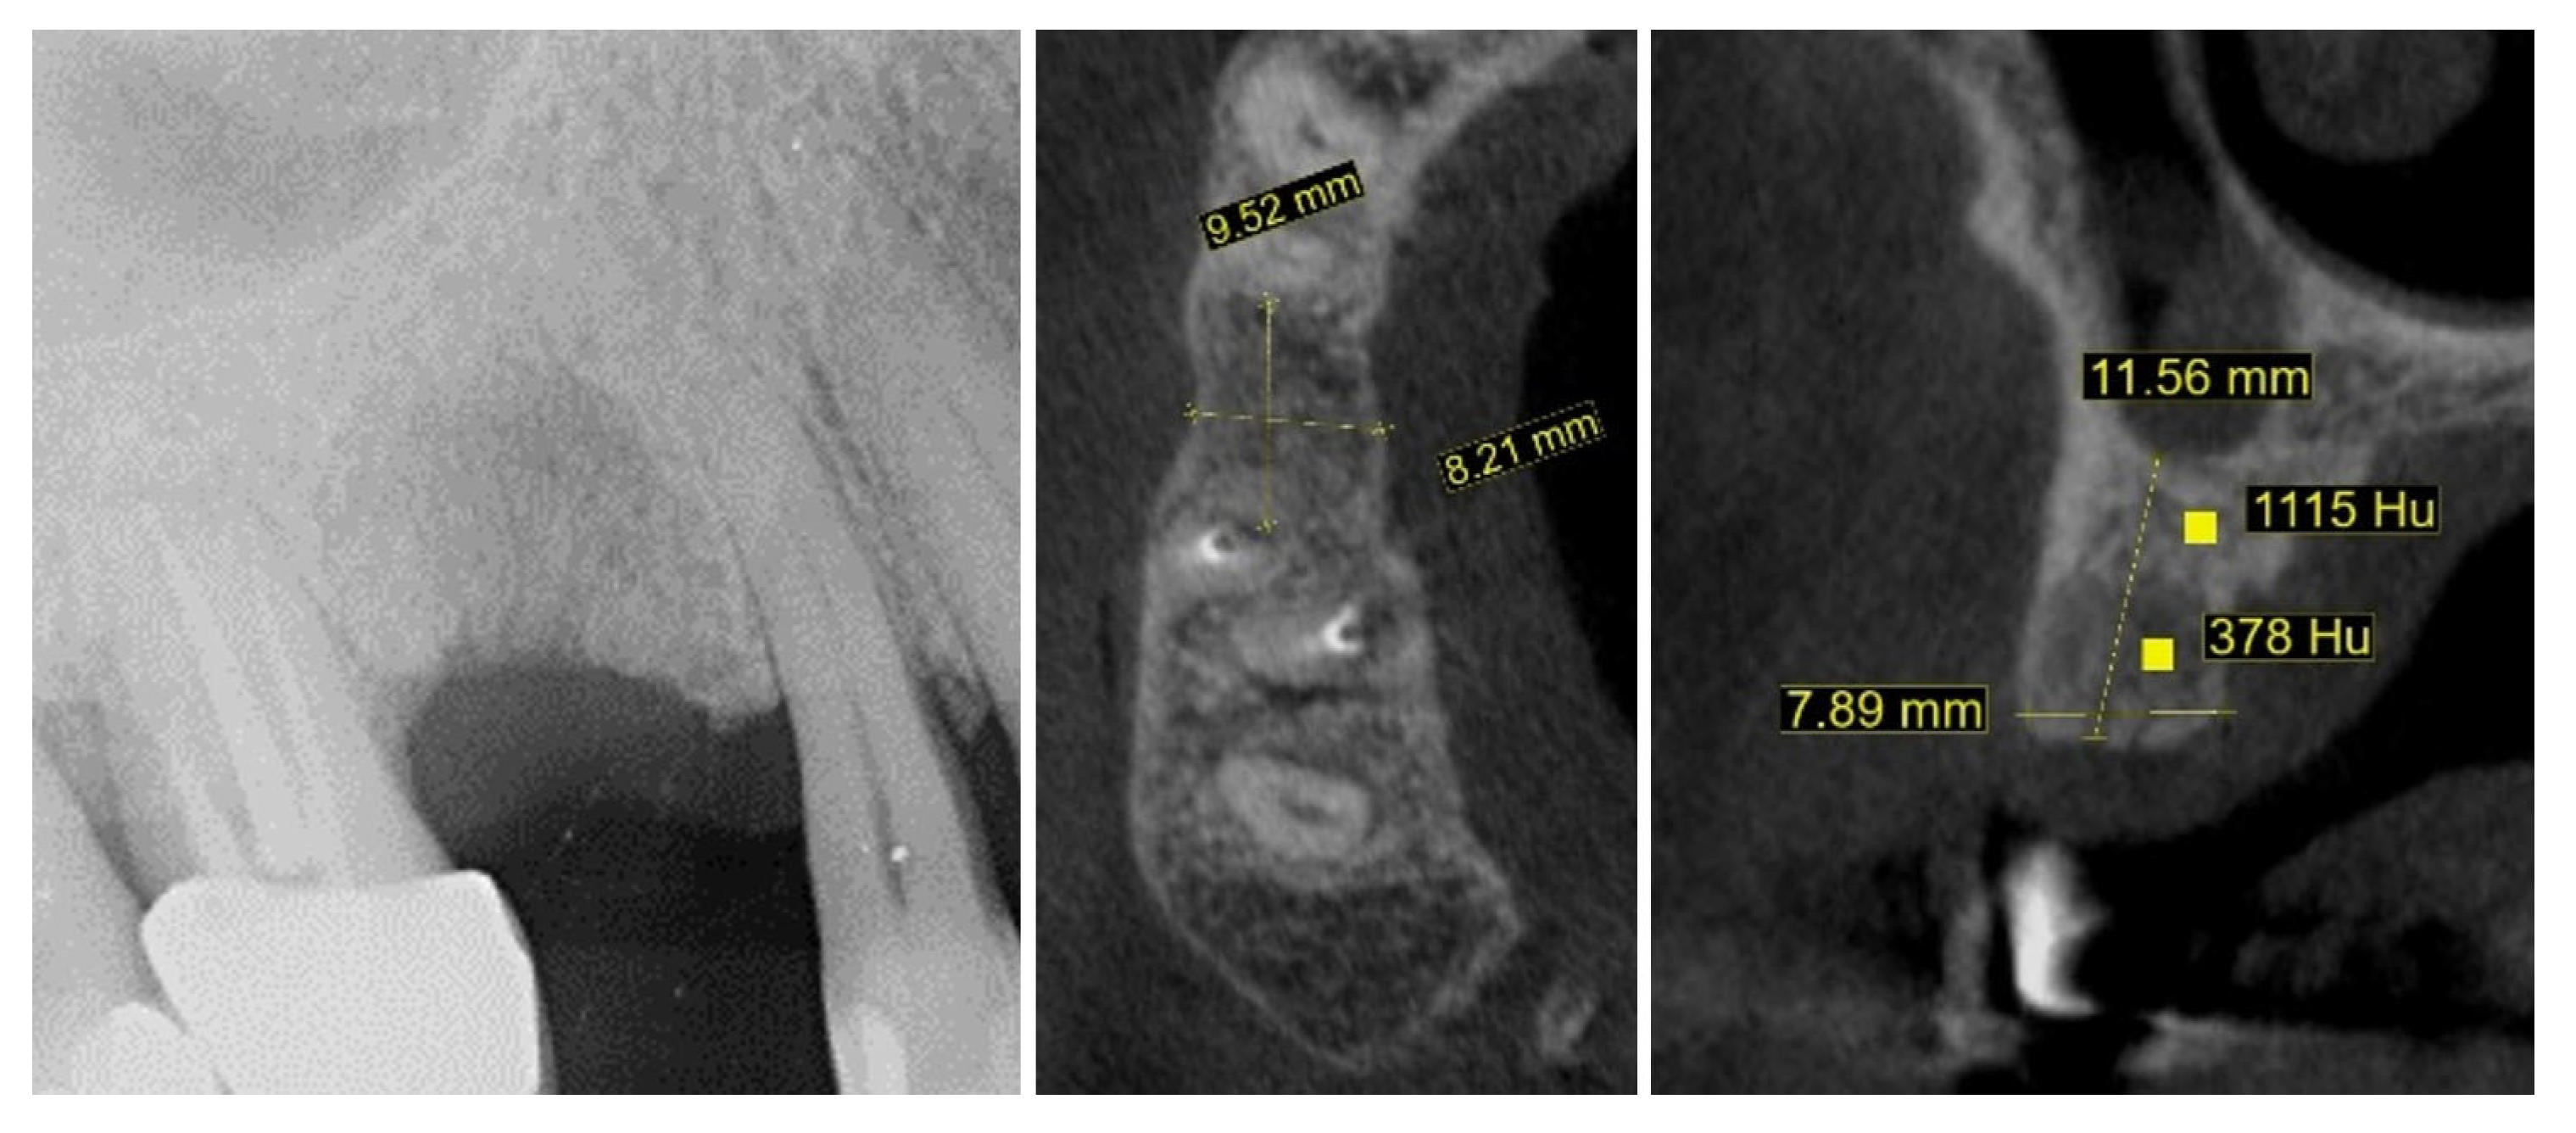

2. Materials and Methods—Clinical Case

| 1 | Baseline (Day 0) | 2.3 | 2.4 | Initial thin buccal tissue |

| 2 | 2 weeks post-op | Uneventful healing, stable mucosal margin | ||

| 3 | 3 months post-op (with provisional) | 3.4 | 3.4 | Increased thickness, stable bone and mucosa |